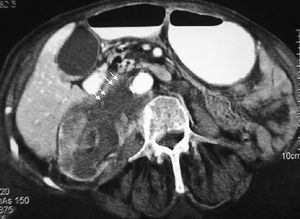

La forma más frecuente es la ausencia de rotación intestinal, que implica importantes alteraciones anatómicas valorables tanto en la ecografía como por la TC. Los principales hallazgos radiológicos son: alteración en la posición del duodeno, que no pasa entre la aorta y la arteria mesentérica superior (AMS); la localización en el hemiabdomen derecho de las asas de intestino delgado y en hemiabdomen izquierdo las de intestino grueso, y una verticalización o inversión de los vasos mesentéricos respecto a su posición normal, quedando la AMS a la derecha y la vena mesentérica superior (VMS) a la izquierda1,2 (fig. 1).

Fig. 1--Malrotación intestinal. (A) y (B) Tomografía computarizada con contraste oral e intevenoso mostrando inversión de la arteria mesentérica superior (AMS) (punta de flecha) y la vena mesentérica superior (flecha). La tercera porción duodenal (D) no cruza la línea media entre la aorta y la AMS, localizándose las asas de yeyuno a la derecha.